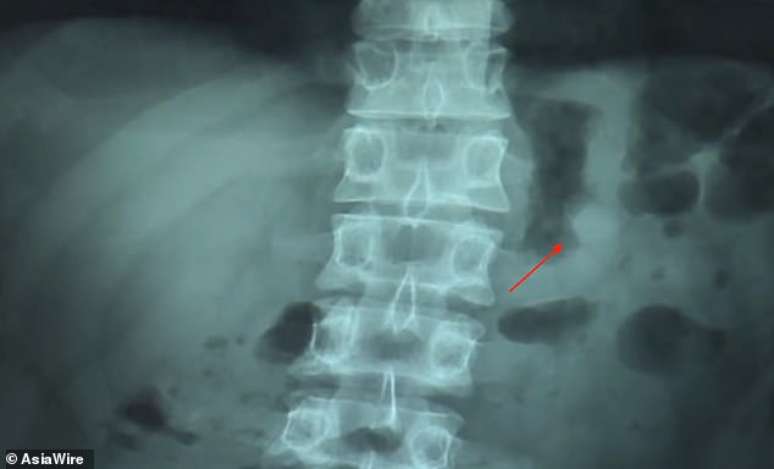

Foto: TecMundo

Levou algum tempo para ele perceber que o fone estava dentro de si. Com a suspeita e a preocupação de estar digerindo uma bateria de lítio no estômago, ele foi a um hospital e tirou a radiografia que você vê a seguir. A imagem confirmou que o fone realmente havia sido engolido durante o sono.

Imagem mostra o que parece ser a cabeça do fone dentro de Ben Hsu (fonte: AsiaWire/Daily Mail)